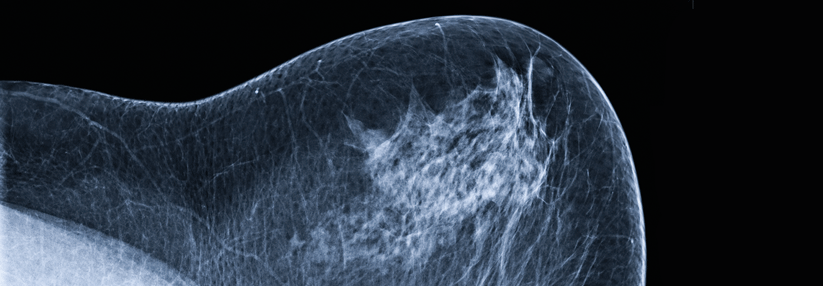

Veliparib plus Carboplatin/Paclitaxel erhöht die Ansprechrate signifikant. Veliparib plus Carboplatin/Paclitaxel erhöht die Ansprechrate signifikant. © Science Photo Library/Charles, Cindy

Die Bedeutung der PARP-Inhibition beim BRCA-mutierten Mammakarzinom wird seit Jahren untersucht. In einer randomisierten Phase-II-Studie verbesserte nun Veliparib zusätzlich zu Carboplatin/Paclitaxel bei BRCA1/2-mutiertem, fortgeschrittenem Mammakarzinom signifikant das Ansprechen.